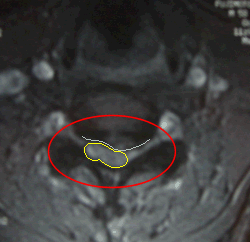

ヘルニアの水平断面

■水平断面

写真右(患者さん左)に飛び出して神経が圧迫されている状態が見られます。